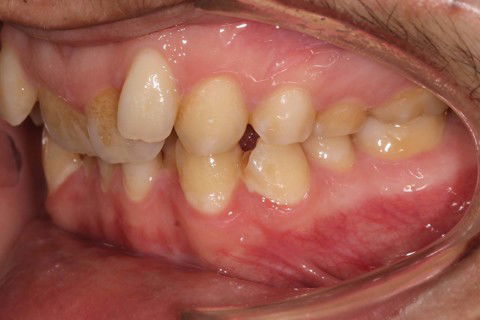

Inicial L. Dir

Paciente: Sexo masculino, 16 anos

Queixa principal: Apinhamento

Diagnóstico: Classe II, divisão 2

Sugestão de Tratamento: Tratamento ortodôntico com o uso do sistema de alinhadores removíveis Invisalign. Sem extrações dentarias, pois o perfil do paciente não era favorável. Por ser um paciente jovem, optou-se por uma expansão dentária controlada, buscando a remodelamento dos arcos.